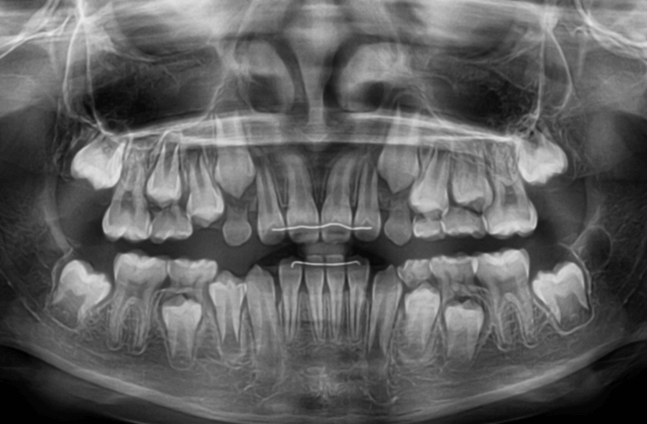

| 年齢・性別 | 8歳3ヶ月の男児 |

|---|---|

| 主訴 | 上顎前歯の位置異常に不安を抱え、歯並びと将来的な咬合状態を整える目的で来院された患者様です。 特に左側の前歯(中切歯および側切歯)の萌出が確認できないことがきっかけとなりました。 |

| 治療期間・回数 | 約5年10ヶ月 |

| 費用 | 460,000円(税別) |